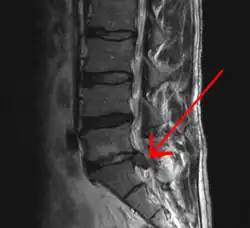

![]() Imagen por resonancia magnética que muestra una hernia discal | ||

La hernia discal es una enfermedad en la que parte del disco intervertebral (núcleo pulposo), que se encuentra entre las vértebras, se desplaza hacia la raíz nerviosa, la presiona y produce lesiones neurológicas derivadas de esta lesión. Pueden ser contenidas (solo deformación, también llamada protrusión discal) o con rotura.[1]